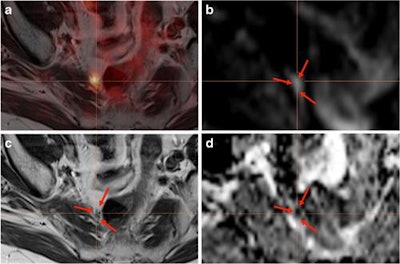

Among the subjects, 71 (61%) underwent PSMA-PET/MRI (Biograph mMR, Siemens Healthineers) scans. Patients received an intravenous injection of 2 MBq/kg Ga-PSMA-HBED-CC conjugate 11 an hour prior to PET/MRI. The PET protocol included a 3D-acquisition technique and an axial field-of-view (FOV) of approximately 23 cm and a transversal FOV of 45 cm.

Results from the PET/CT and PET/MRI scans were interpreted by an experienced reader for prostate hybrid imaging, while CT and MR images were assessed by a uroradiologist.

In analyzing the results, the researchers discovered 100 of the 117 patients had at least one PSMA-avid lesion, for a detection rate of 85%. Most importantly, PSMA-PET was the only modality to provide diagnostic information for 67 (67%) patients, with no morphologically suspicious correlation with CT or MRI. In the remaining 33 (33%) cases, both standard CT or MRI and PSMA-PET detected the positive lesions.

PSMA-positive lesions were confirmed through either histology (16%), PSA decrease in metastasis-directed radiotherapy (45%), or additional information in diffusion-weighted MR imaging (18%) in 79% of patients. In fact, the detection rate for PSMA-PET increased in relation to PSA values.